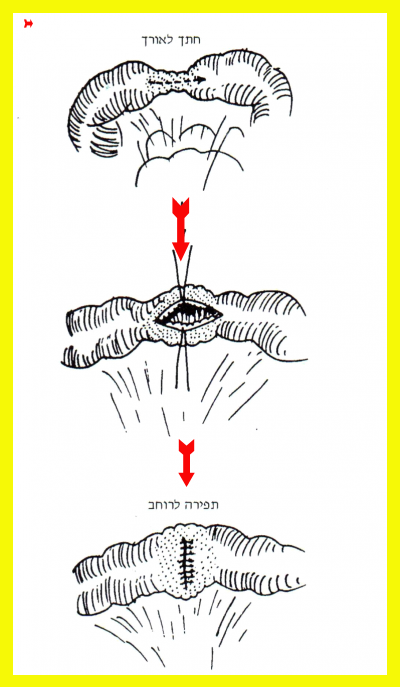

הסטריקטורופלסטיקה היא גישה "מינימליסטית" בכירורגיה של מחלת קרוהן ותוארה בתחילת שנות ה-80. בניתוח זה מבצעים חיתוך לרוחב הסטריקטורה (או לאורך המעי) ותפירת החתך לאורך הסטריקטורה (או לרוחב המעי). ניתוח זה מאפשר הרחבת האזור המוצר (איור 4.4).

הוכח כי השיטה של תיקוני היצרויות בלא כריתה (Strictureplasty) היא בטוחה, וקרוב לוודאי אינה כרוכה בסיבוכים ואינה מסכנת את החולה בהישנות מוקדמת יותר בהשוואה לכריתה המקובלת. שיטה זו של התגברות על היצרויות חוסמות, בלא הקרבת קטעי מעי, מתאימה לשימוש לאורך כל דרכי העיכול, ומשמשת חלופה מועילה בעיקר לכריתות נרחבות או מרובות לנוכח מחלה מפושטת לסירוגין לאורך המעי הצם והכרוך. השיטה מתאימה במיוחד גם לטיפול בהיצרות התריסריון. שיטות המעקף ששימשו לטיפול בבעיה זו רחוקות מלהשביע רצון. התיקון הרוחבי של היצרויות החלק השני והחלק השלישי של התריסריון, הוכח כישים. על היצרות החלק הרביעי אפשר להתגבר באמצעות השקה צד לצד בין החלק המורחב לבין המעי הצם בצמוד לרצועת טריץ (Treitz).